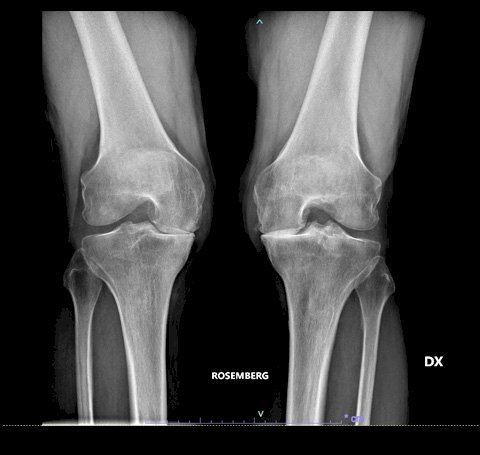

Una volta che l’ortopedico si è fatto un’idea delle funzionalità del ginocchio è necessario eseguire un primo esame diagnostico attraverso i Raggi X, al fine di valutare l'entità del danno presente. Alcuni casi spingono i chirurghi a richiedere anche un’indagine diagnostica più approfondita attraverso una risonanza magnetica, al fine di valutare le condizioni di cartilagine e legamenti.

In basso le lastre preoperatorie di un pz con gonartrosi mediale.